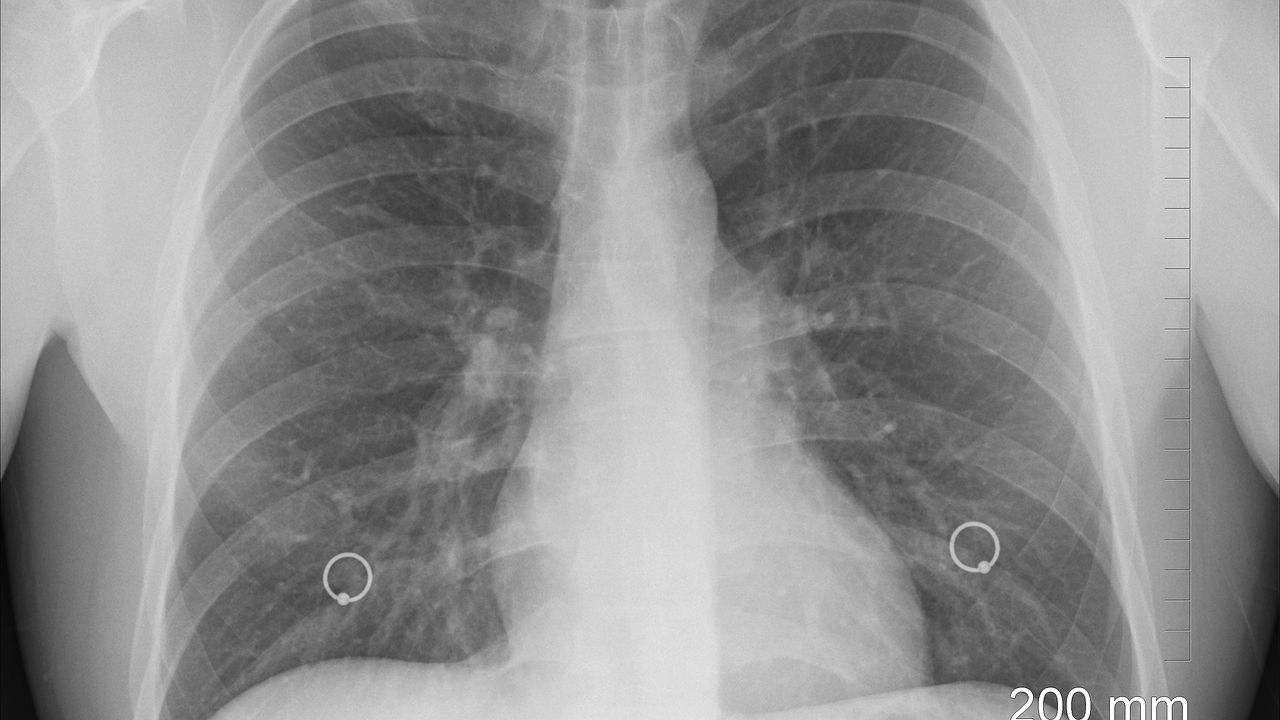

Liječnici upozoravaju da mnogi građani dugotrajni kašalj pripisuju gripi ili Covidu-19, dok bi uzrok zapravo mogla biti tuberkuloza – bolest koja je nekada bila gotovo iskorijenjena, ali se sada ponovno širi u pojedinim dijelovima zemlje. Tuberkuloza, uzrokovana bakterijom Mycobacterium tuberculosis, najčešće napada pluća, ali može zahvatiti i mozak, kralježnicu ili bubrege. Simptomi uključuju uporan kašalj dulji od tri tjedna (često s ispljuvkom ili krvlju), vrućicu, noćno znojenje, umor, gubitak težine i apetita. Ako se ne liječi, može uzrokovati trajna oštećenja pluća ili smrtonosne komplikacije poput meningitisa ili zatajenja organa, javlja Daily Mail.

Iako je rizik za širu populaciju nizak, tuberkuloza se lako širi bliskim kontaktom s zaraženom osobom putem kašljanja, kihanja ili govora. Posebno zabrinjava porast slučajeva otpornih na više antibiotika, koji čine 2,2% laboratorijski potvrđenih slučajeva – najviša razina od početka praćenja 2012. godine. Ovi slučajevi zahtijevaju duže i složenije liječenje, što dodatno opterećuje zdravstveni sustav. Stopa incidencije u Engleskoj trenutno iznosi 9,4 slučaja na 100.000 stanovnika, što je ispod vrhunca od 15,6 iz 2011., no stalni porast ukazuje na ozbiljan javnozdravstveni izazov. London bilježi najvišu regionalnu stopu s 20,6 slučajeva na 100.000, a slijedi West Midlands s 11,5. Bolest je češća u urbanim područjima i usko je povezana s deprivacijom, a 82% prošlogodišnjih slučajeva zabilježeno je među osobama rođenima izvan Ujedinjenog Kraljevstva.